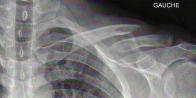

Le médecin tâte mon épaule. Pour elle ce n'est pas nécessairement une fracture, ça pourrait être juste démis. À voir. Donc radio. Et quand j'ai vu la radio, j'ai rapidement compris que ce n'était pas une luxation. C'est une bonne vieille fracture, pas d'hésitation possible.

Du coup : pas de vélo pour moi pendant un certain temps. Compliqué de faire les brevets qualificatifs pour Paris-Brest-Paris dans ces conditions. Compliqué aussi de se préparer pour le Triple Ironman de Lensahn. Mais bon on va voir. J'attends de voir la suite, pour l'instant j'ai mon petit harnais qui me tient les épaule en arrière pour que ça ressoude à la bonne longueur, des médocs pour ne pas avoir trop mal parce que je suis une chochotte, et je vais faire contrôler tout ça à l'hosto la semaine prochaine.